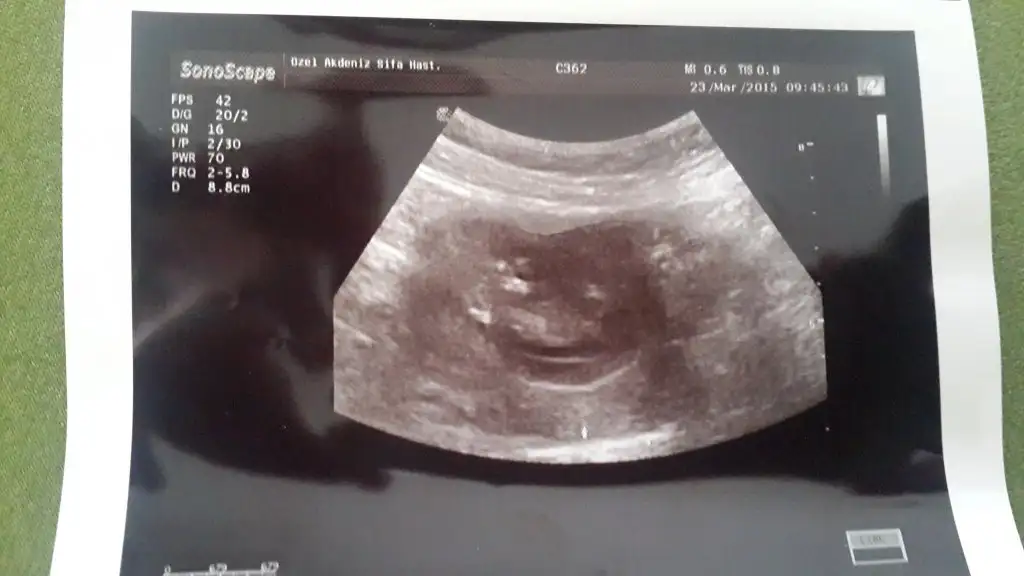

Canım benim Bebeğimi de yorumlarmisiniz 11+4 haftalik fotosu

mrb kizlar bende tahminlerinizi bekliyorum sat a gore 11+4 ultrasyon a gore 12 + 0